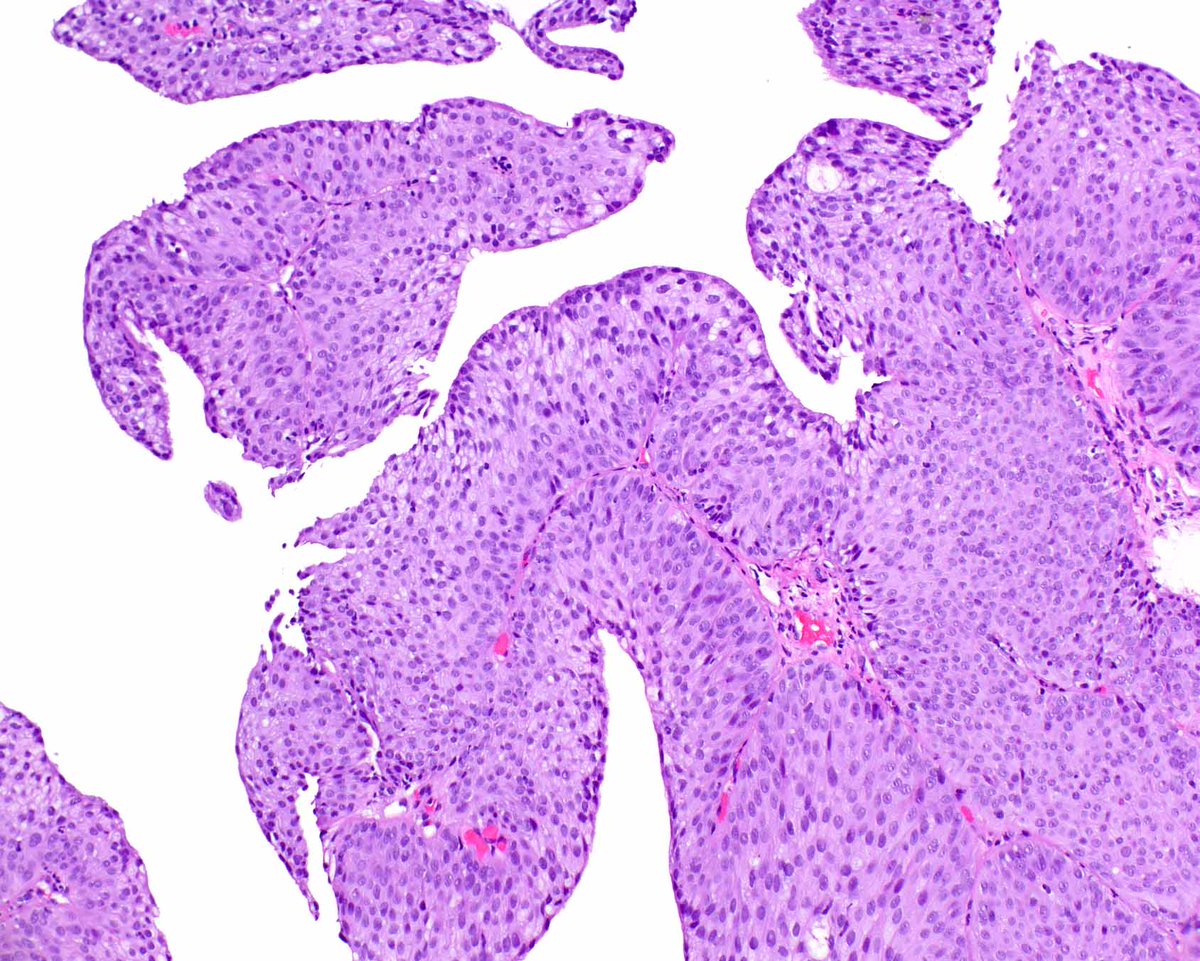

Our GI Pathology Fellowship has an unexpected opening for July 2026. Dr. Ortiz (right) and I are the program directors. We have superb cases and excellent colleagues (Drs. M. Garcia, R. Yantiss, S. Al Diffalha, O. McDonald). Send your CV to adriana.zanaty@miami.edu